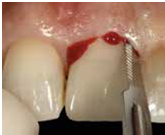

2) 以不翻瓣,無傷害的方式移除牙齒: 先以15c刀片切開supracrestal fiber, 必要時切割牙齒 (fig 8,9)

3)以surgical curette或bur清乾淨齒槽窩, 檢視齒槽窩壁; 特別留意齒槽窩必須有完整的頰側骨壁(不低於free gingival margin 4mm)

4) 將植體依正確位置放入; 植體位置需稍偏palatal且植體的頂部需稍低於頰側骨嵴 (在free gingival margin下3-4mm) , 植體的咬面觀離頰側骨壁約有2mm 的空隙 (fig 10,11)

(Fig 7,8,9)

(Fig 10,11)